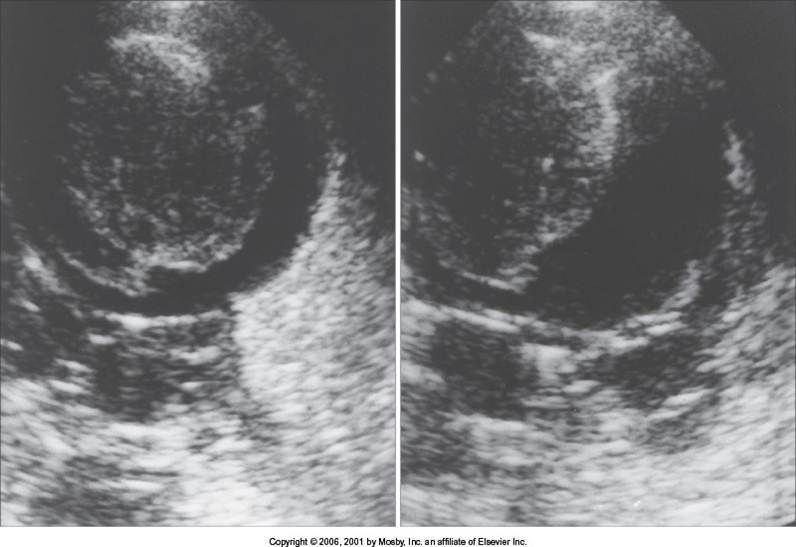

Chronic Hep

Inglamatory process of liver is longlasting

lead to cirrhosis and liver failure

SONO

bumpy borders, hertero, fiobrosis is a disease process that gives liver coarse texture.